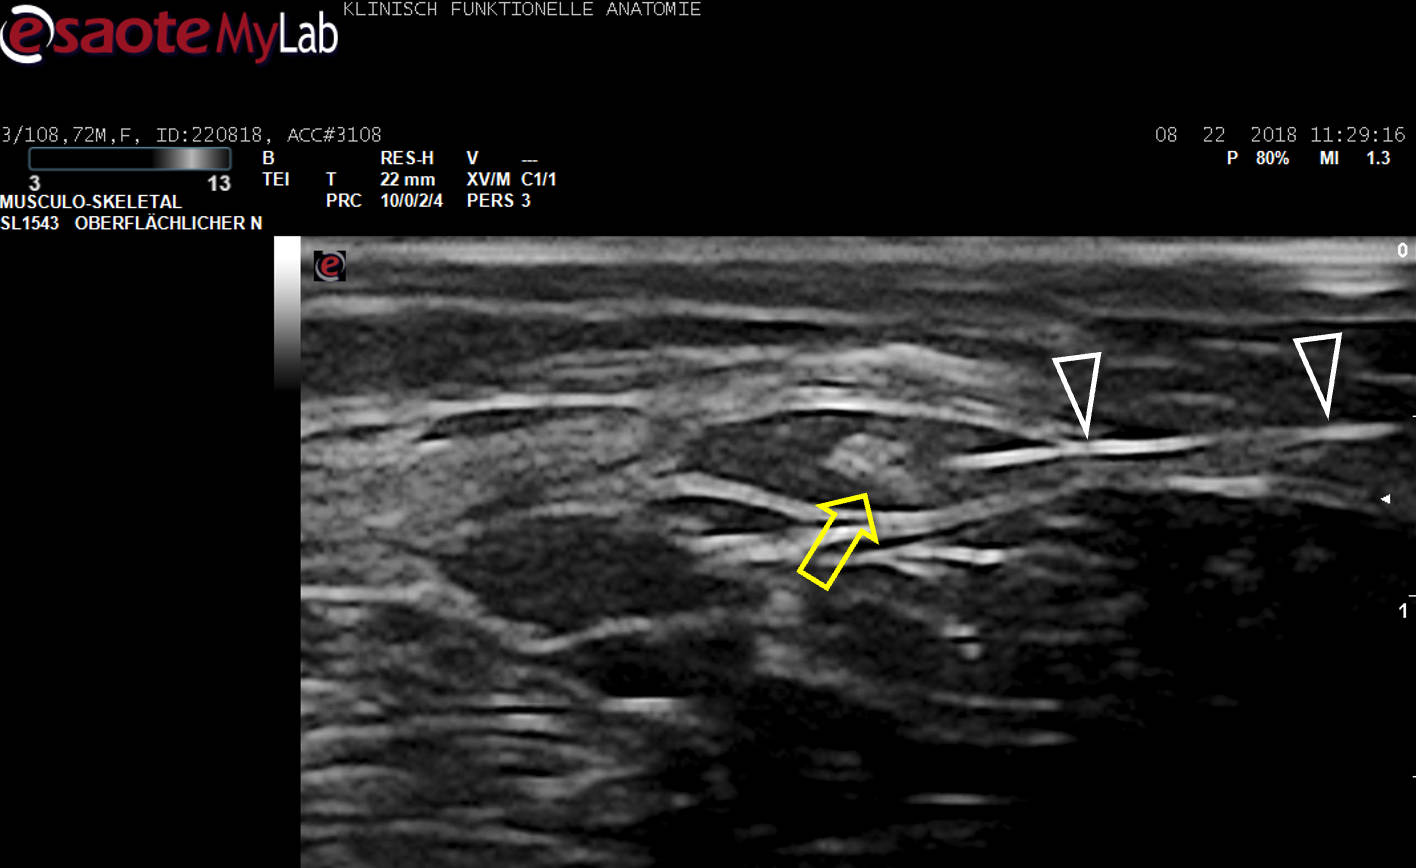

Aus unserer Grundlagenarbeit zur Anwendung des Ultraschalls (US) in der Schmerztherapie: Optimierte Darstellung zur sicheren Blockade des N. occipitalis major bei Occipitalis-Neuralgie. Heute wird der Nerv im klinischen Alltag weltweit nur noch an dieser Stelle US-gezielt blockiert!

US-Darstellung und experimentelle Blockade (Pfeilköpfe: Nadel) des N. cutaneus femoris lateralis an einer Körperspenderin. Mittlerweile gängige Anwendung in der Regionalanästhesie und Schmerztherapie